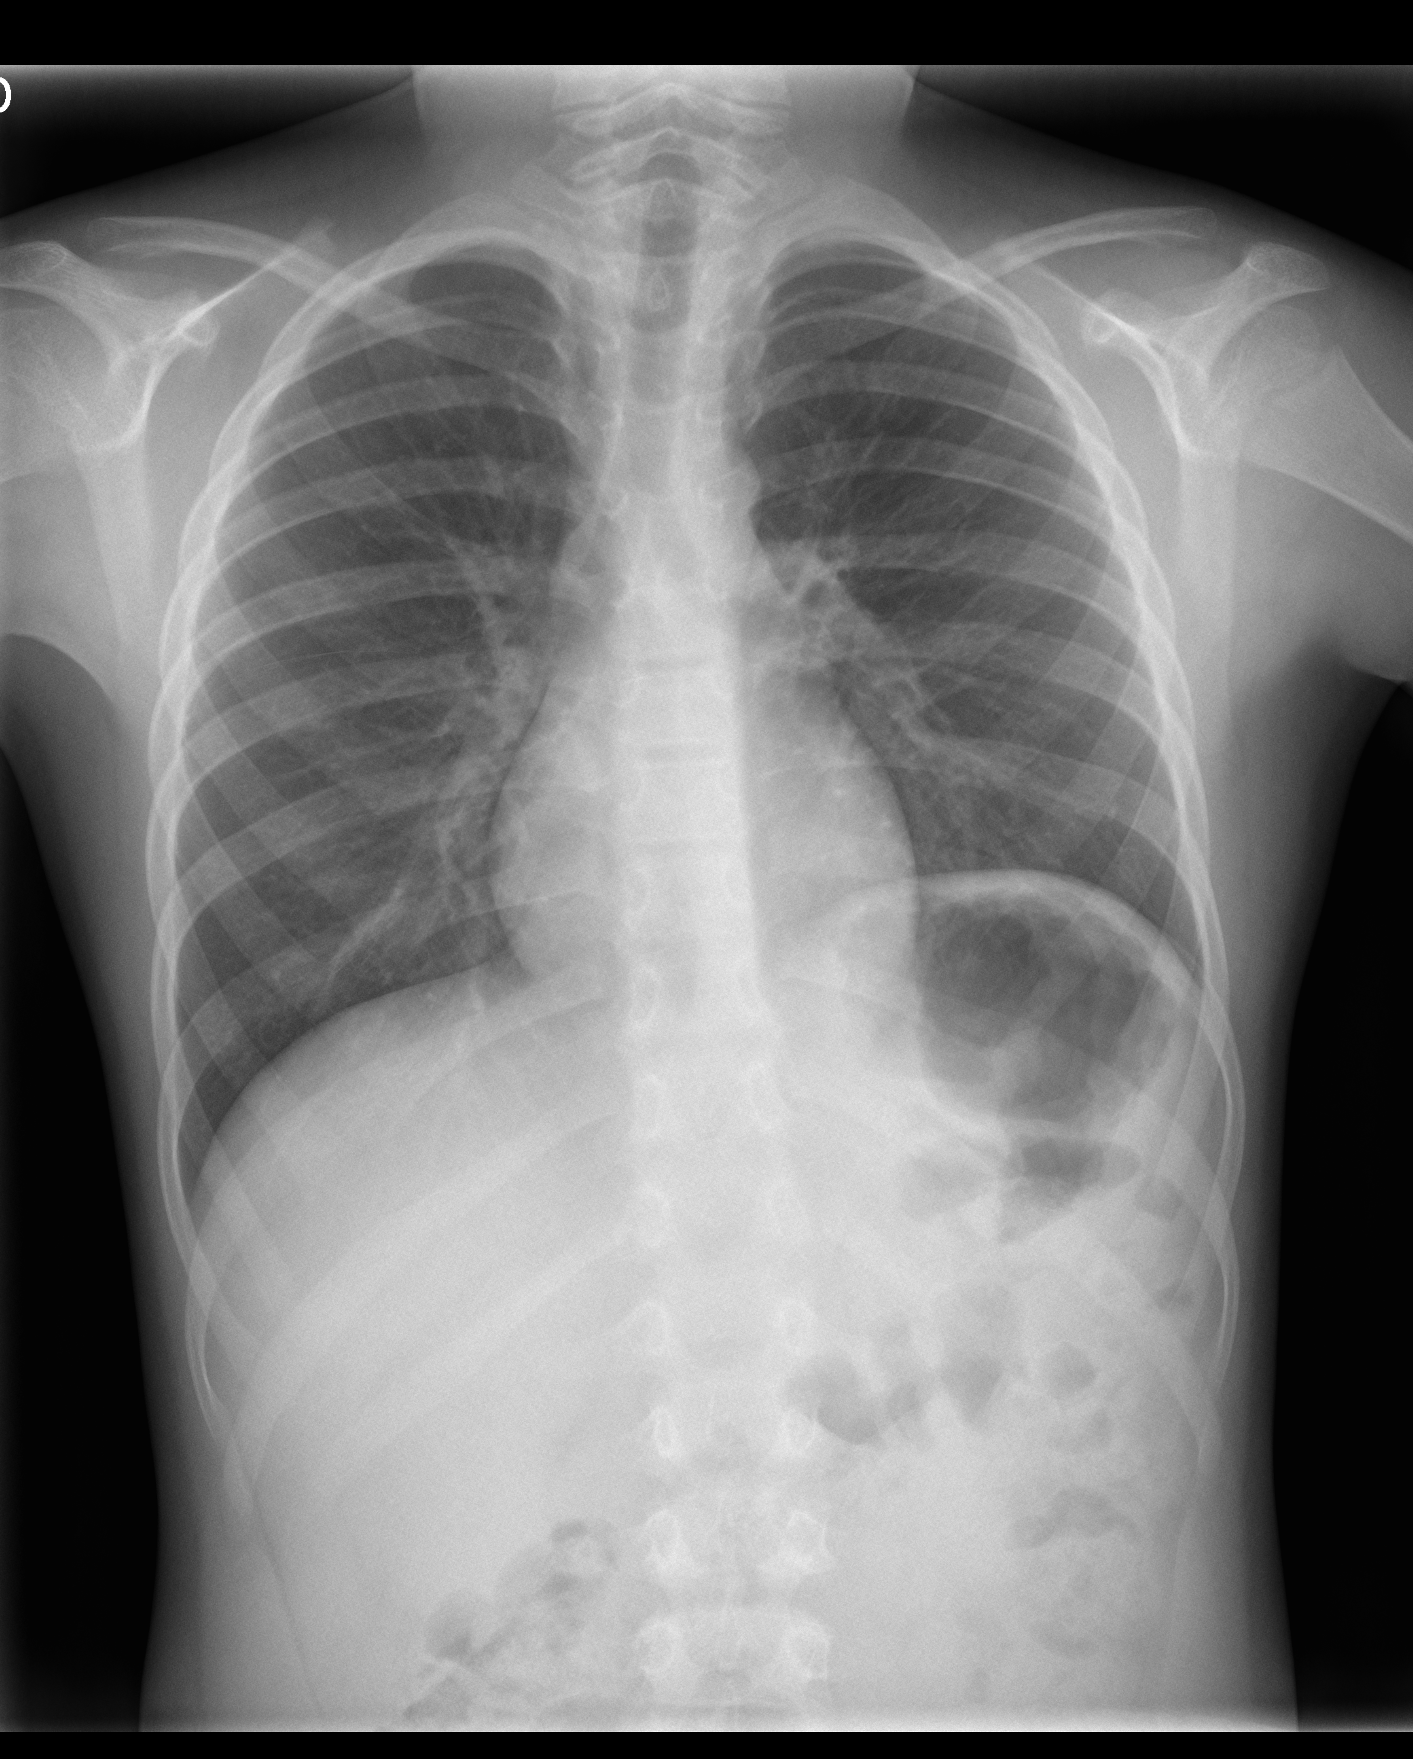

Rx Simple AP: Masa mediastínica anterior izquierda.

Leve atelectasia en língula. Elevación del hemidiafragma izquierdo